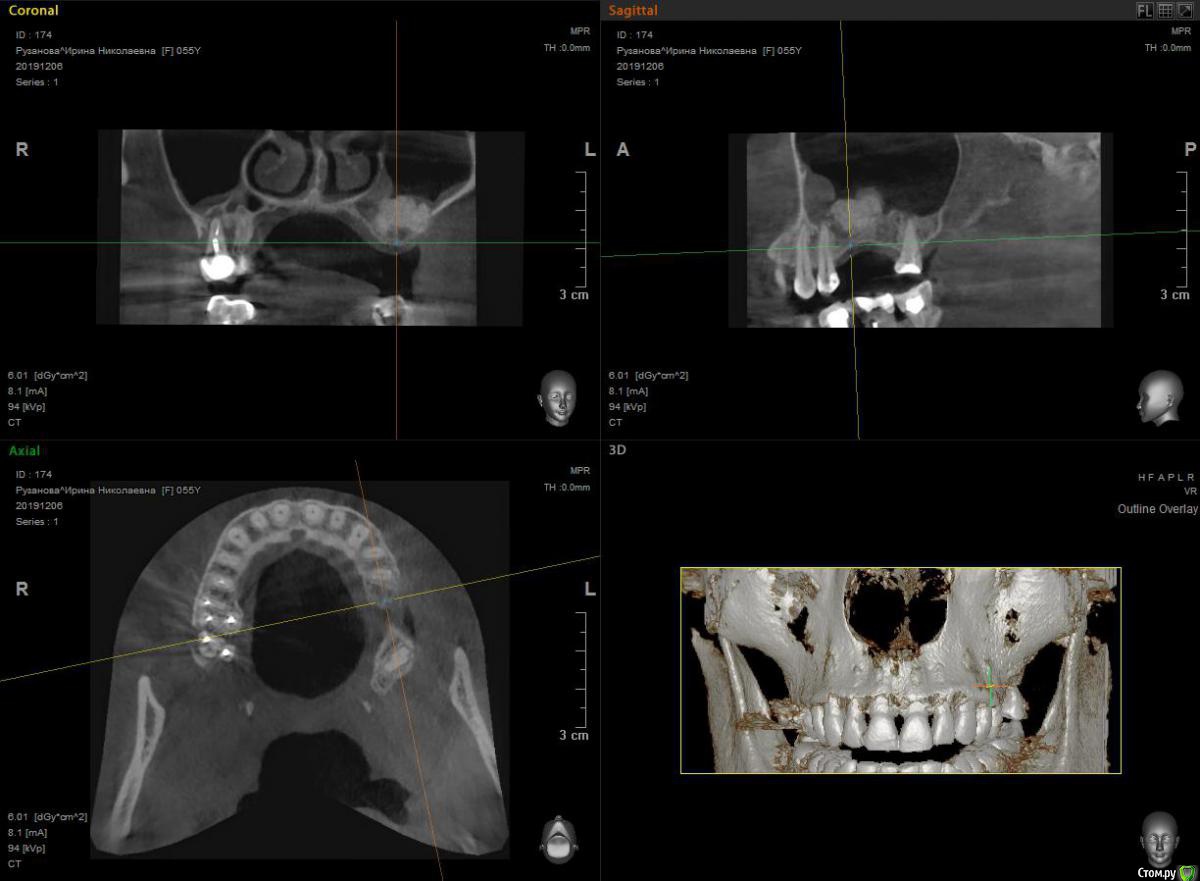

HAV Опубликовано 18 мая, 2020 Поделиться Опубликовано 18 мая, 2020 Всем здравствуйте. Была проведена операция ОСЛ, во время проведения операции была перфорация слизистой оболочки пазухи, перфорация закрыта интраоперационно мембраной Bio-Gide, внесен графт CeraBone. Первый снимок через 5 месяцев после операции - результат неудовлетворительный. Предпринята попытка повторно выполнить ОСЛ, старался максимально заполнить пустоты графтом, но как видно на снимке полностью исправить ситуацию не удалось. На даннный момент прошло 6 месяцев после последней операции. Интересует ваше мнение - возможно ли в данной ситации установка имплантата в позиции 26 зуба? Устанавливать имплантат в позиции 27 зуба пациенткка не хочет. Ссылка на комментарий